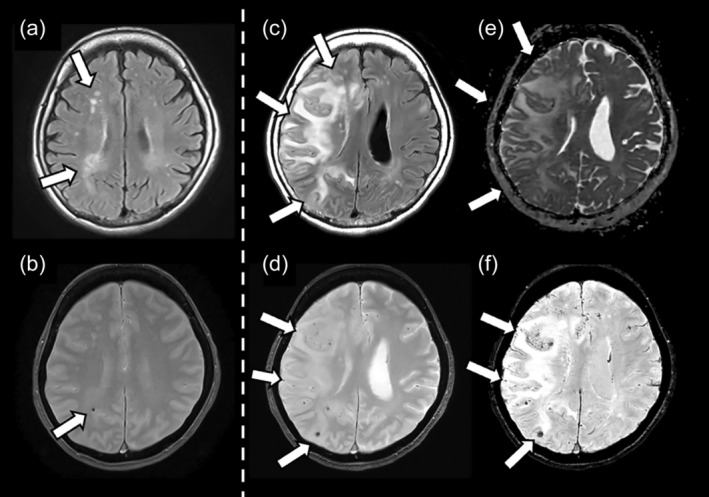

A case of severe ARIA with multiple infarctions and extensive microbleeds following lecanemab administration.